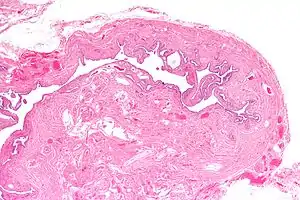

| Micrograph of salpingitis isthmica nodosa, showing the characteristic nodular thickening. H&E stain. | |

Salpingitis isthmica nodosa (SIN), also known as diverticulosis of the Fallopian tube, is nodular thickening of the narrow part of the uterine tube, due to inflammation.

It is characterized by nodular thickening of the tunica muscularis of the narrow (isthmic) portion of the Fallopian tube. In severe cases, it leads to complete obliteration of the tubal lumen. It is uncommonly bilateral.[2]

Microscopic Findings:

- Glandular epithelium within tubal muscularis propria, in continuation with mucosa or (more commonly) discontinuous

- Haphazard distribution (akin to adenomyosis) or pseudoinfiltrative

- Banal epithelium with tubal differentiation[4]